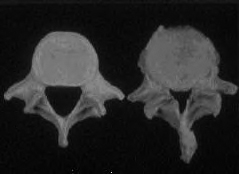

Die weitaus meisten Rückenprobleme sind duch einen relativ früh beginnenden Verschleissprozess der Wirbelsäule bedingt.